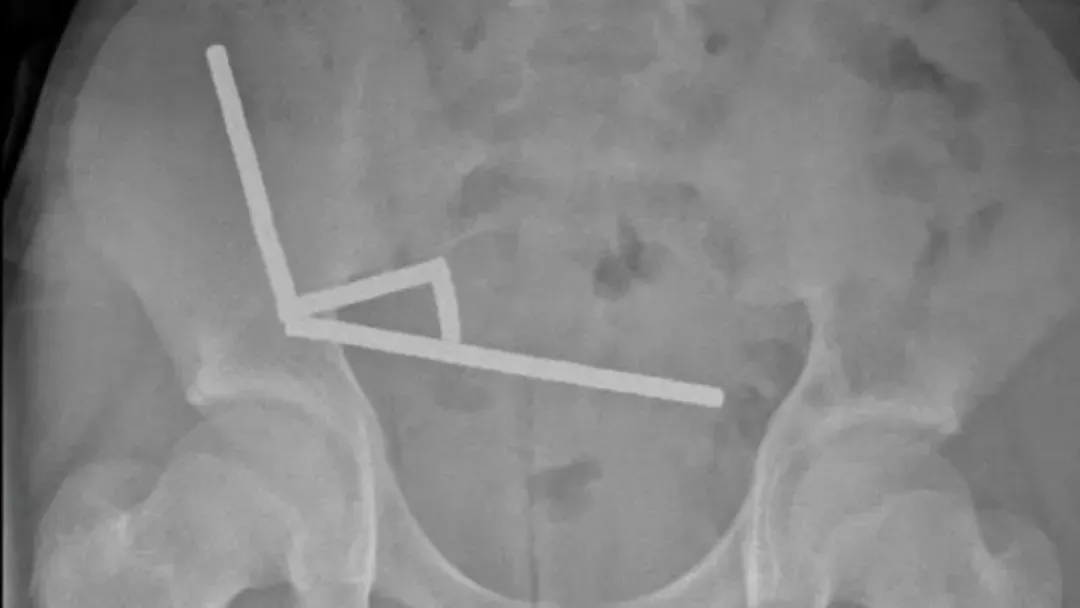

医生通过 X 光片观察到,男孩肠道的不同部位出现了四条线状的磁铁链。

手术中发现,这些磁铁链分别位于小肠不同区段及盲肠内。它们相互挤压,导致多处组织因血液供应不足而坏死,这种现象被称为压迫性坏死。

腹部 X 光片显示了磁铁分布情况 来源:Lekamalage et al.,?NZMJ, 2025